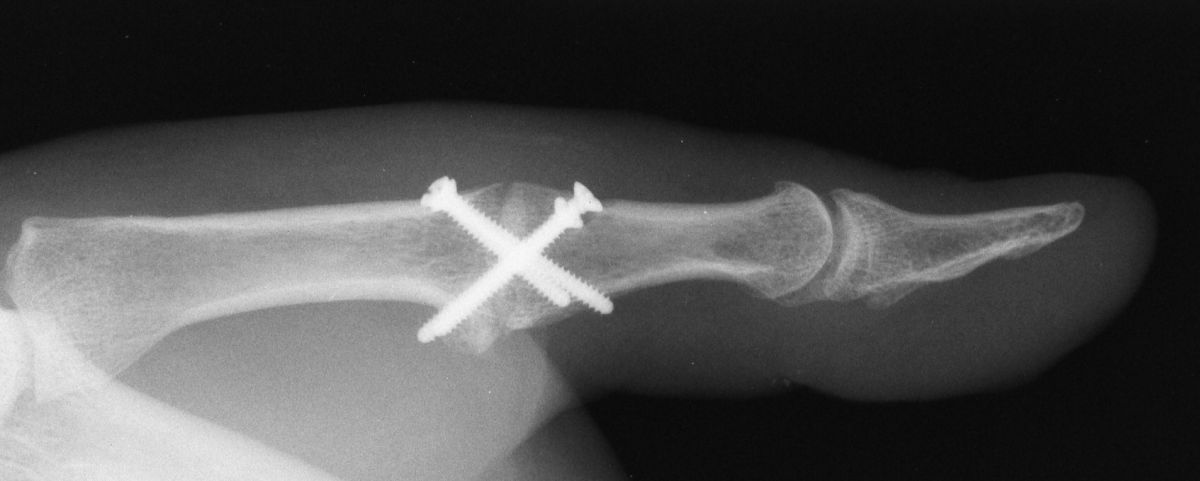

| This patient had chronic

pain and instability from an old radial collateral ligament rupture

| The Synthes mini fragment

system was used, with a lag screw across the fusion site and

sesamoid excision. |

| Although the patient healed

uneventfully, the screws seem excessively large for these bones. |